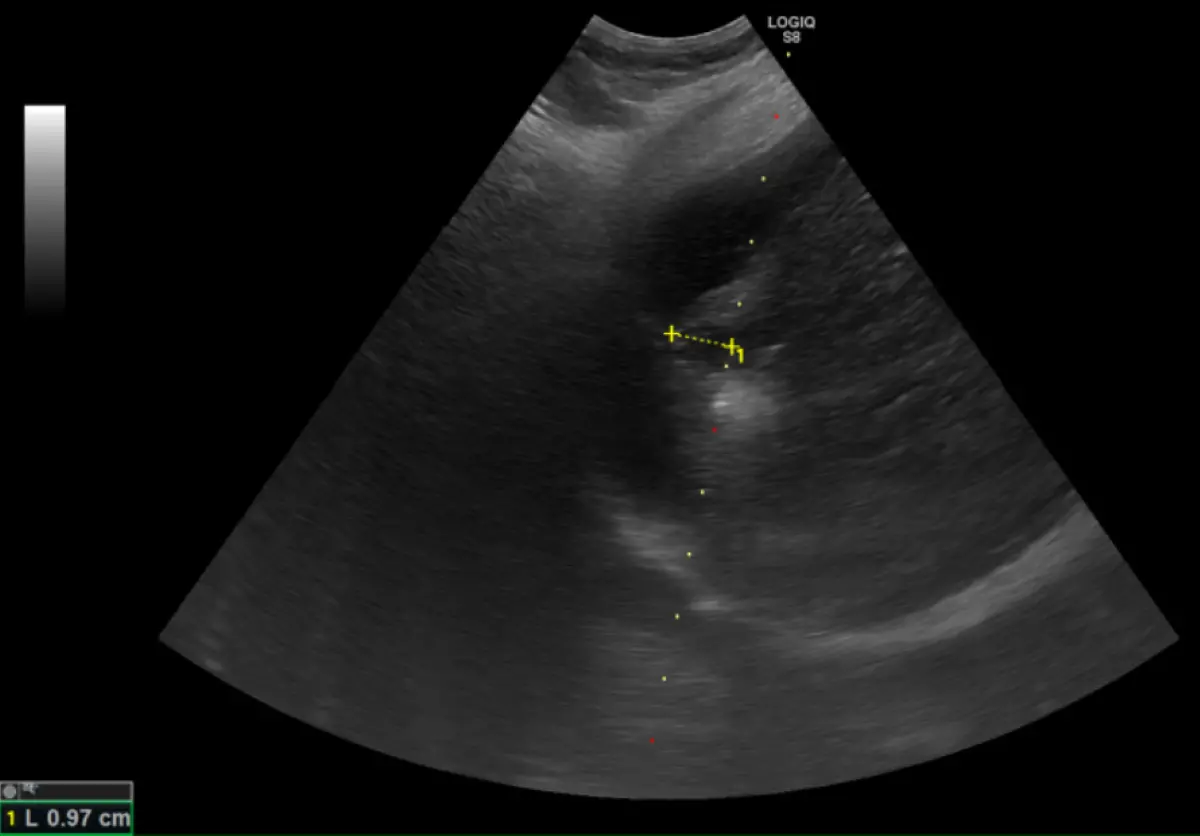

針對零期肝癌,鄭煜明表示,治療後平均存活率可超過10年,若延至第2期僅約5年,第3期降至2年半,第4期更僅半年;他也說,零期使用電燒治療普遍可根治,不需化療,且目前電燒治療透過超音波導引,透過電極產生熱能氣化腫瘤,得以較以往保留更多健康肝臟組織。